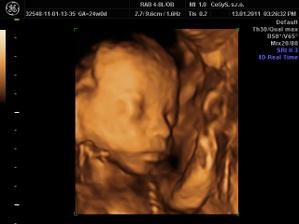

Naša lásočka 13+0tt...už teraz ju milujeme!)))